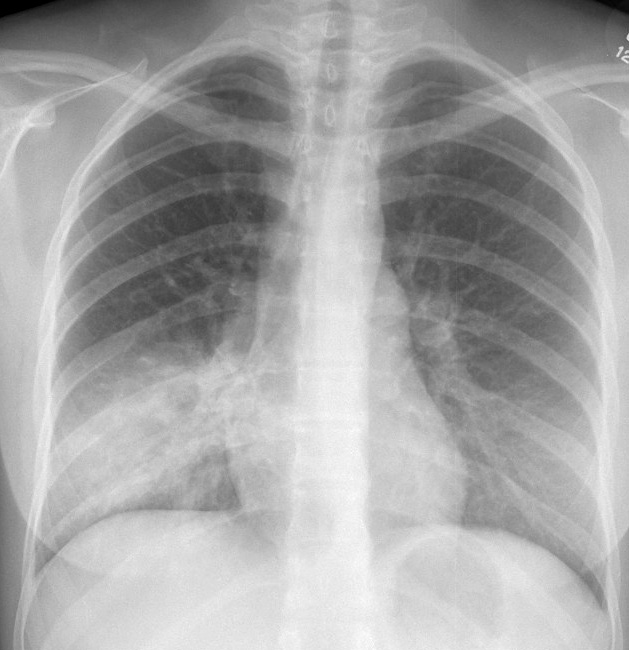

Pneumonia

Case 6 RLL pneum PA

Date: 04/17/2005